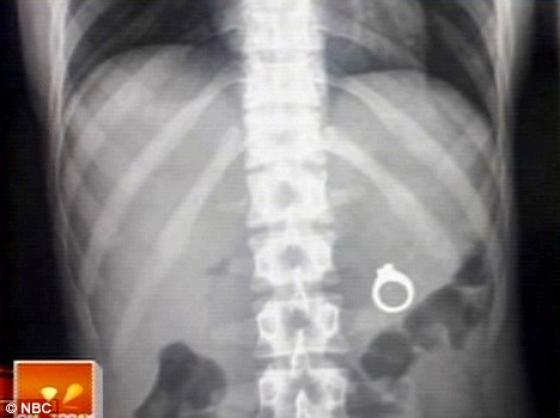

Le couple a dû partir à l'hôpital où une radio a confirmé ce qui s'était passé. C'est ainsi que le jeune homme a posé son genou à terre et, avec une copie du scanner à la main, a fait sa demande en mariage, que la jeune femme a acceptée.